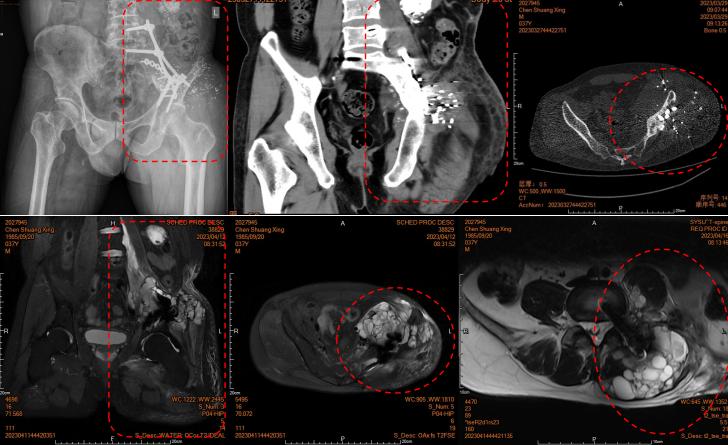

▲术前影像提示左侧骨盆巨大软骨肉瘤复发伴骶骨、多个腰椎及椎管内侵犯(红色边框显示肿瘤切除范围)